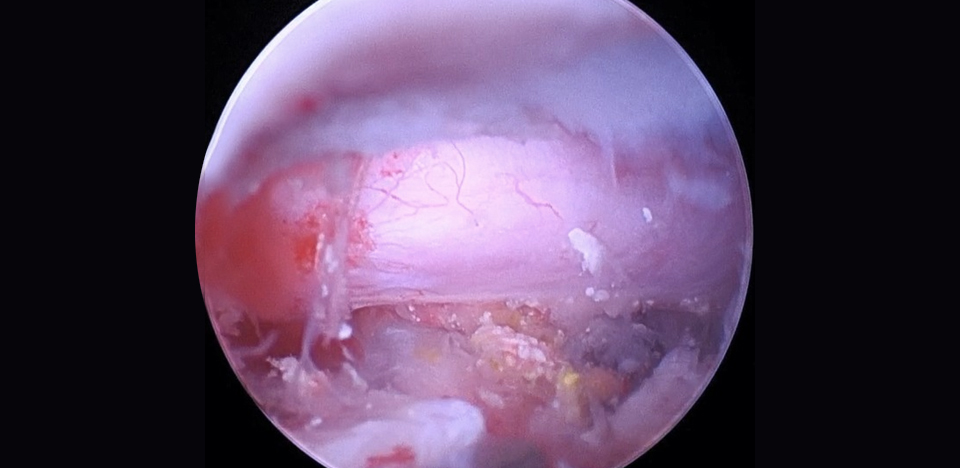

관절 내시경 수술

• 관절 내시경 수술은 관절 내부에 가느다란 카메라를 삽입해 관절면과 연골, 인대 구조를 직접 확인하며 치료하는 방법입니다.

• 작은 절개만으로 관절 내부의 병변을 정확하게 진단하고 불필요한 조직을 제거하거나 수술 치료를 시행할 수 있습니다.

• 관절낭 절개 없이 관절안을 선명하게 관찰할 수 있어 진단 정확도가 높고 수술 후 통증이 현저히 줄어듭니다.

• 슬개골 탈구, 십자인대 손상, 관절 내 신생물 등 다양한 관절 질환에서 빠른 회복과 낮은 합병률을 기대할 수 있습니다.